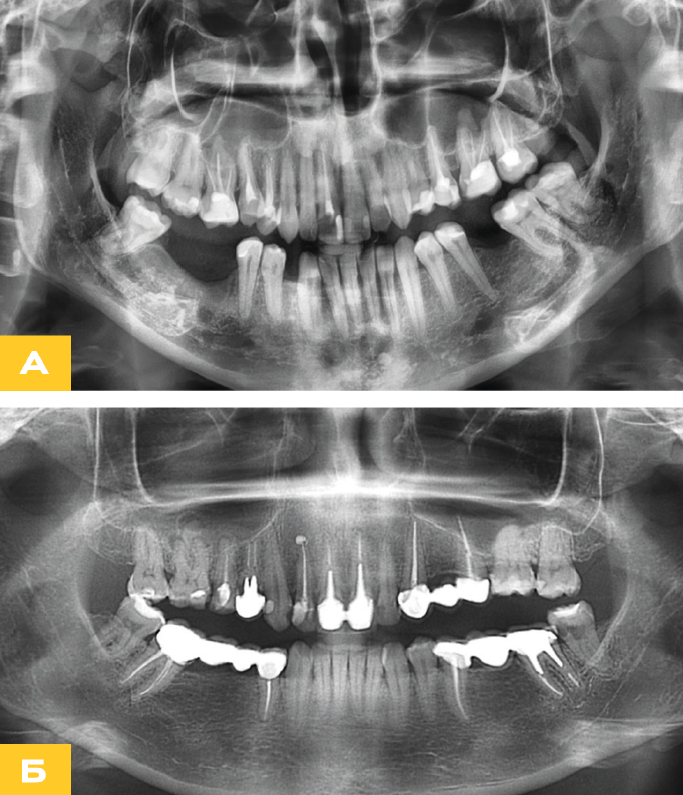

Медицинские Исследования: Кортикальная Пластинка на ОПТГ